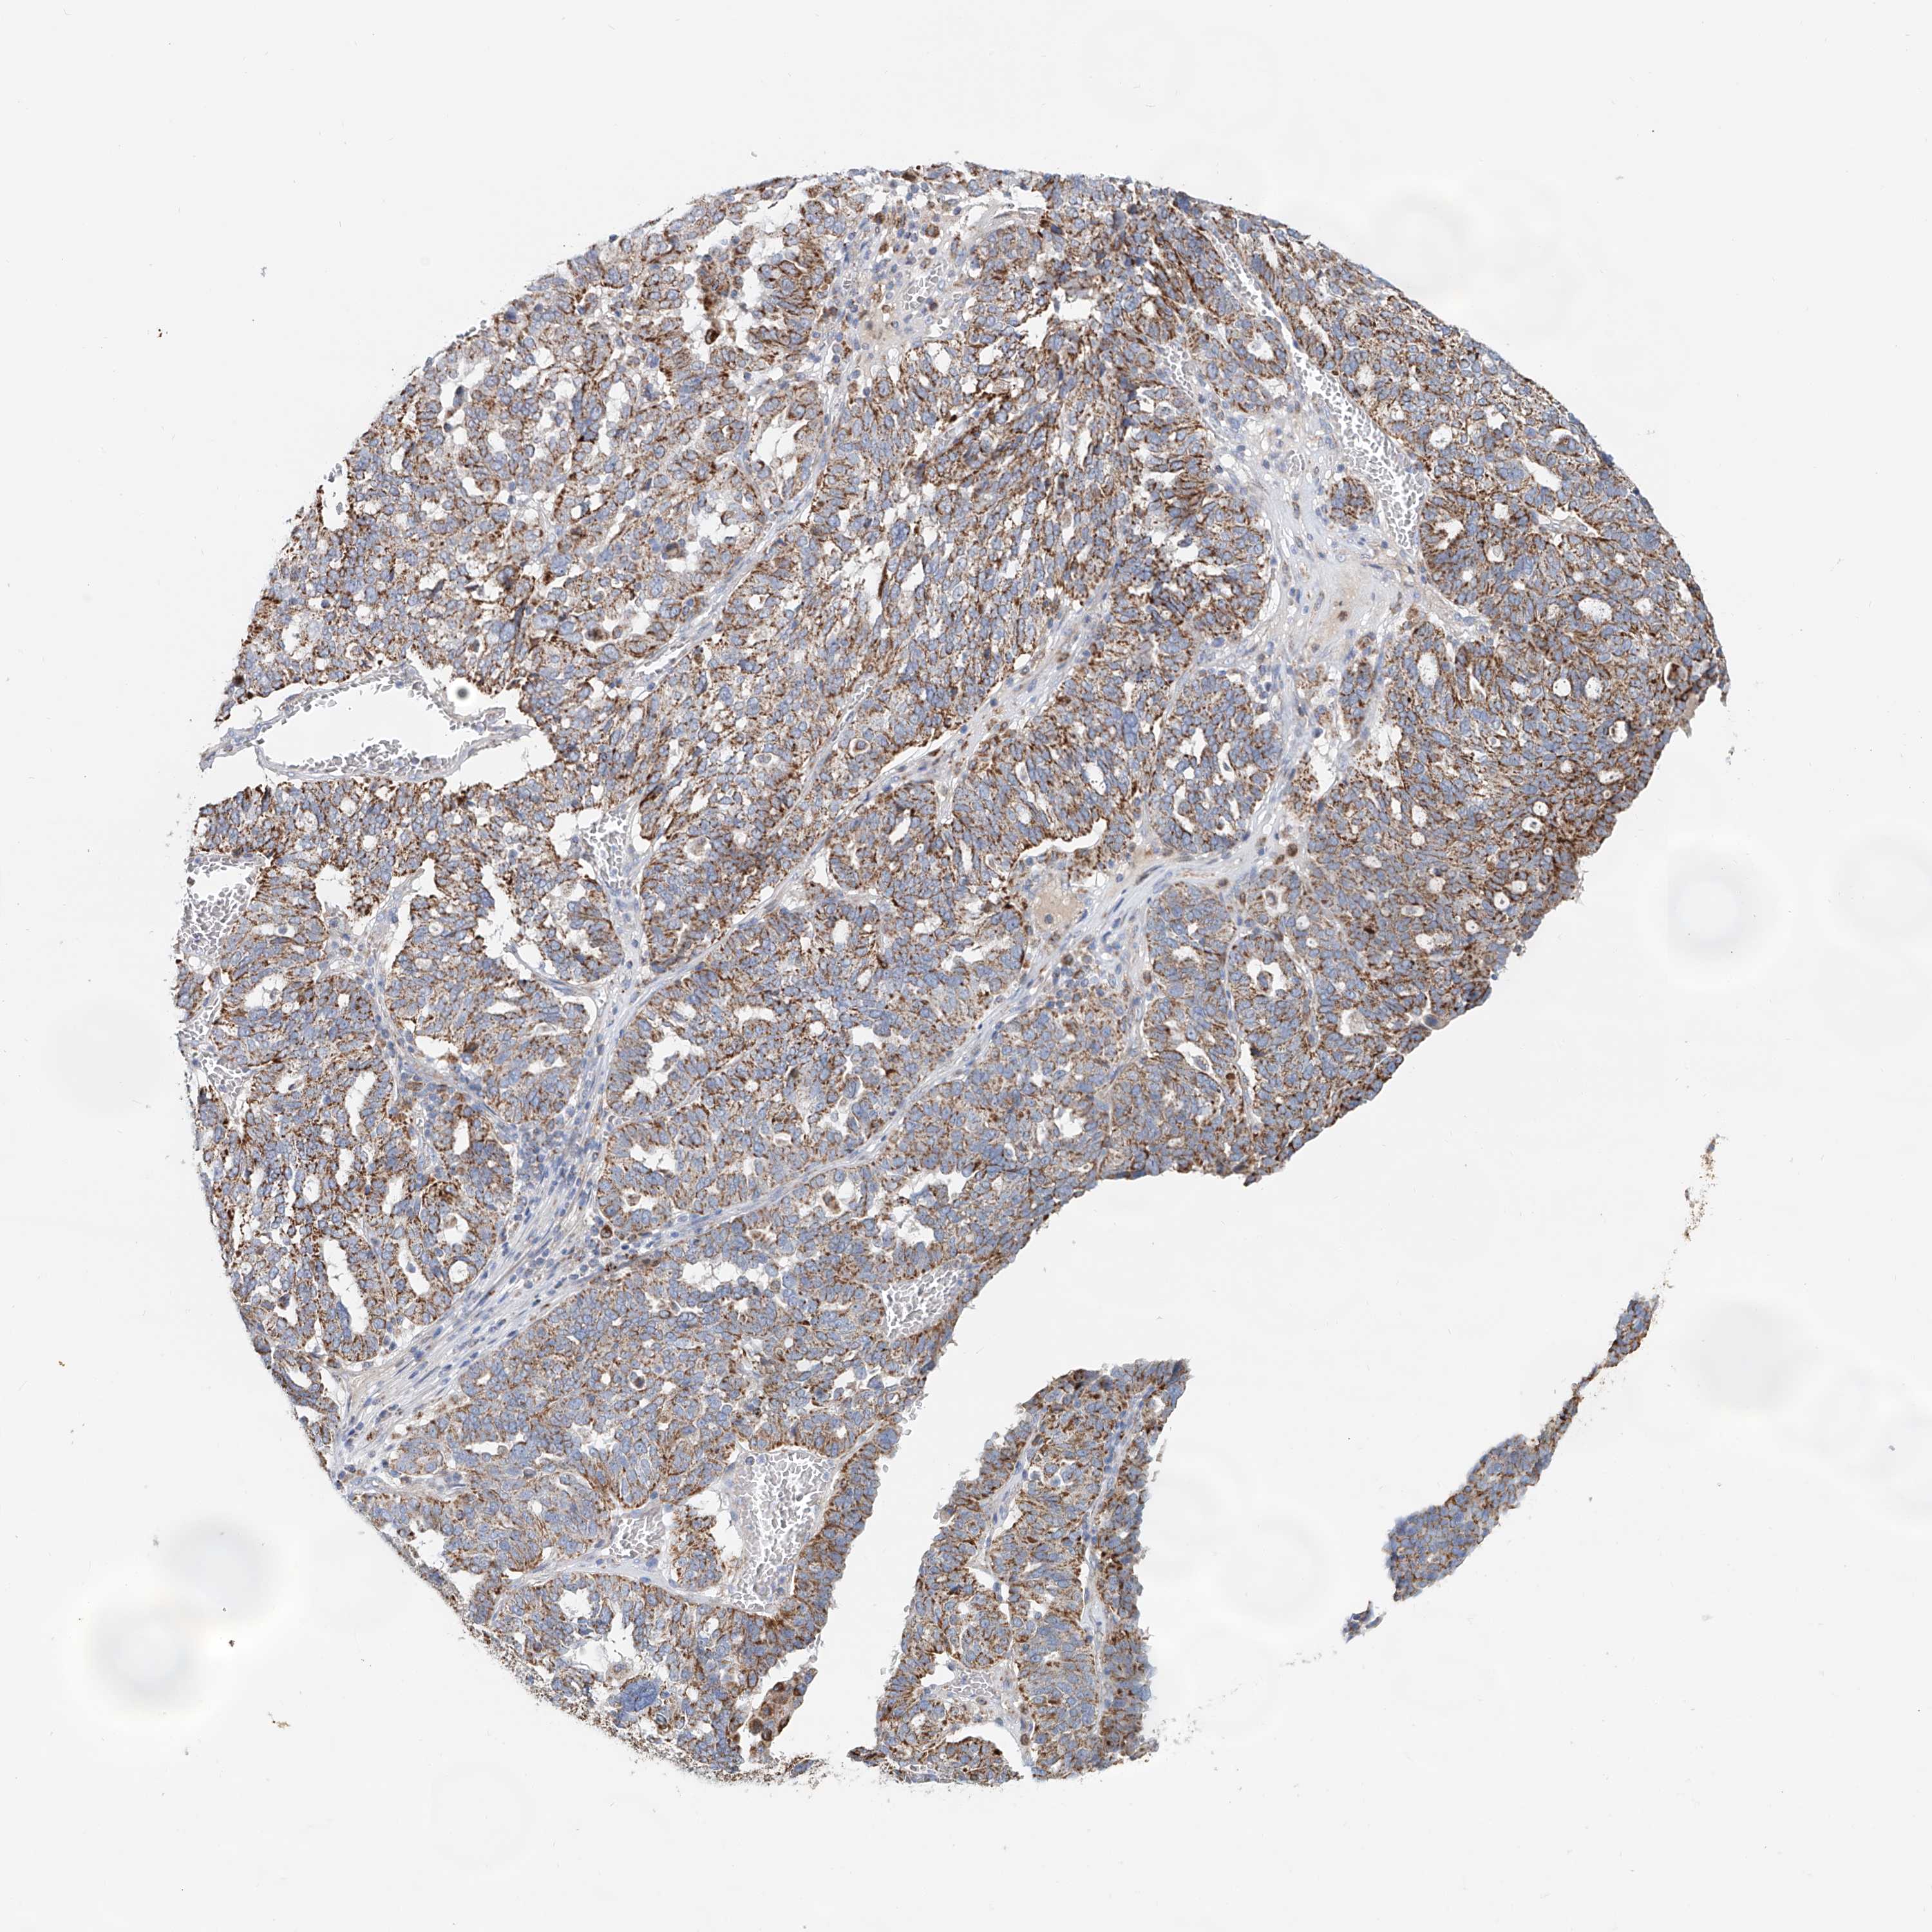

OVARIAN CANCER - Protein expressioni

A mouse-over function shows sample information and annotation data. Click on an image to view it in a full screen mode. Samples can be filtered based on level of antibody staining by selecting one or several of the following categories: high, medium, low and not detected. The assay and annotation is described here.

Note that samples used for immunohistochemistry by the Human Protein Atlas do not correspond to samples in the TCGA dataset.

Antibody stainingi

Antibody staining in the annotated cell types in the current human tissue is reported as not detected, low, medium, or high, based on conventional immunohistochemistry profiling in selected tissues. This score is based on the combination of the staining intensity and fraction of stained cells.

Each image is clickable and will lead to virtual microscopy that enables deeper exploration of all samples and also displays staining intensity scores, fraction scores and subcellular localization as well as patient and tissue information for each sample.

Antibody HPA029359

Staining

High

Medium

Low

Not detected

Intensity

Strong

Moderate

Weak

Negative

Quantity

>75%

75%-25%

<25%

None

Location

Nuclear

Cytoplasmic/membranous

Cytoplasmic/membranous,nuclear

Cystadenocarcinoma, serous, NOS

Carcinoma, endometroid

Cystadenocarcinoma, mucinous, NOS

Carcinoma, NOS